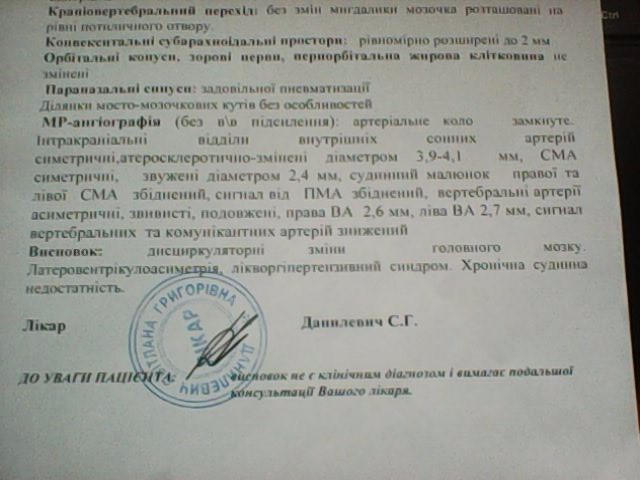

МРТ головного мозга: Расшифровка снимков и Интерпретация

Раздел: Визуальные уроки